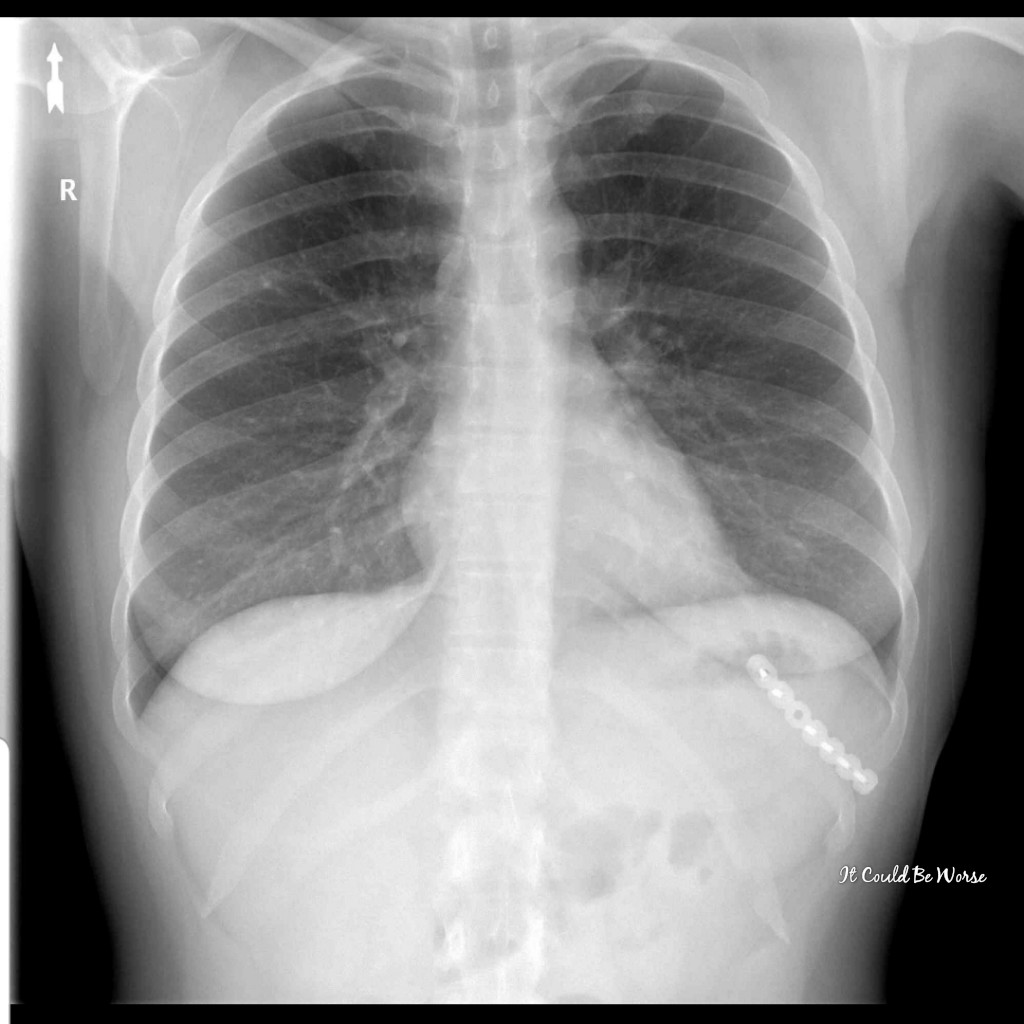

I went to the emergency room on the Monday following my Friday primary care visit. I had x-rays done, again, with nothing seen, again.

I was given muscle relaxers and meds for inflammation with a shot of Toradol in my butt. The Toradol was painful, like a Penicillin shot – those of us in the Navy call those ‘Peanut Butter shots’ because they are thick and they hurt.

View X-ray #2